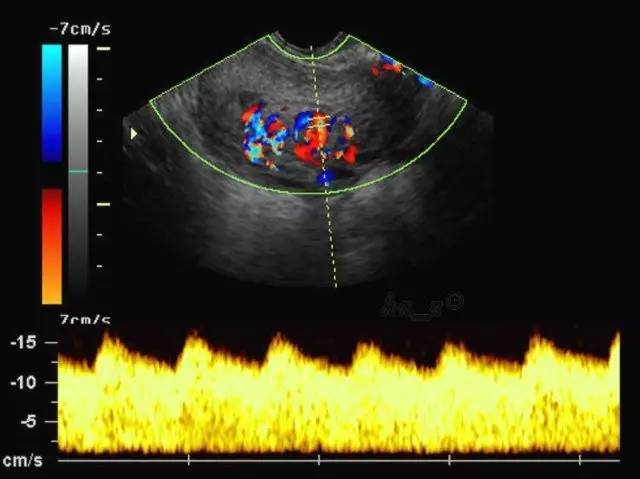

通俗点时候,普通B超和彩超归为一个范畴:普通B超就像黑白照片,彩色B超就是在B超的功能上多了一个彩色多普勒功能(CDFI),可以在黑白图像上看到彩色的血管,当彩色多普勒功关闭的情况下,它依然是黑白B超超声。

(彩超图)